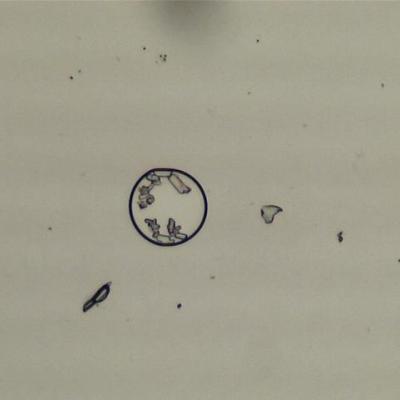

Здравствуйте, после встречи с одной незнакомкой... появился вопрос к специалисту. Встречались мы с ней два месяца. После секса у меня на лобке были красные высыпани. Мелкие разрозненные красные точки, которые проходили сами по себе через день. Иногда небольшая боль в яичках. У нас всегда был прерванный половой акт. Только один раз она попросила кончить в нее и я сделал это. В момент эякуяции я физически почувствовал как что-то в меня заходит. И моментально появилась боль в области спины в низу, ниже поясницы. Эта боль стала нарастать с большой скоростью и мне уже было трудно изгибать тело, то есть любое движение сопровождалось болью. В одном и том же месте, внизу спины. Больше мы с ней не встречались. Анализы (обычные мазки) она сдала и ничего не нашли. У меня эта боль через две-три недели уменьшилась. Это все произошло 5 лет назад. После этой женщины у меня три года была другая женщина и мы всегда использовали кондом. Микроб мой так и остается во мне. Предстательная железа не увеличина и болей в области простаты нет, также и яички... всё как было всегда. Никаких изменений. ВОПРОС К ВАМ И ПРОСЬБА - сделаем вместе диагностику и определим что это за микроб... или вирус. У меня есть микроскоп с увеличением до 2000 и он подключен к компьютеру. Проблема у меня в том что нет опыта. Я не понимаю что на этих фотографиях. Мне нужны ваши знания чтобы квалифицированно обьяснить что мы видим по микроскопом. Естественно, я был на приеме у местных врачей и естественно, они сказали своё слово, но об этом я промолчу. Никакого лечения я пока не начинал и не проводил раньше. Скорее всего у Вас будут дополнительные вопросы... я отвечу честно и подробно. Вот для примера фото с моего микроскопа. Таких фотографий много и можно записать видео... А также, я согласен заплатить за Ваши услуги пятьдесят долларов сша. С Уважением Александр